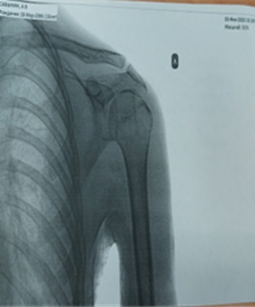

После клинического, рентгенологического обследования был выставлен диагноз: Хроническая рецидивирующая передняя нестабильность левого плечевого сустава. Привычный вывих левого плеча (рис. 1). Дежурным травматологом было произведено закрытое вправление вывиха под внутривенным наркозом. Иммобилизация косыночной повязкой. На контрольной рентгенограмме вывих головки плечевой кости вправлен (рис. 2).

Рис. 2. Рентгенограмма левого плечевого сустава после вправления

Примечание: составлен авторами на основе рентгенологического исследования левого плечевого сустава